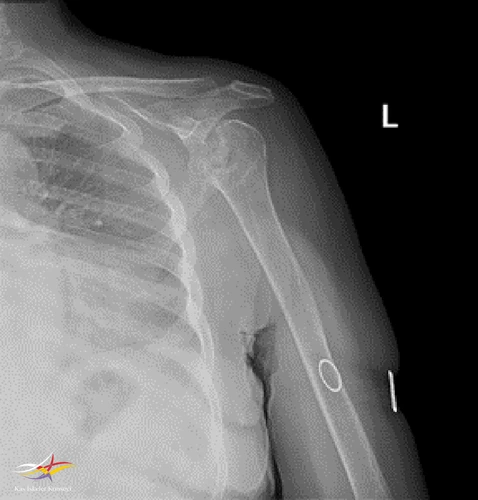

Sol Omuz MRG: Glenoidde kortikal düzensizlikler, lokalize defektif alanlar ve bu düzeyde subkondral milimetrik kistlerin eşlik ettiği medüller hafif hiperintens ödem izlenmektedir. Humerus baş kesiminde medialde de geniş bir alanda defektif görünüm mevcuttur. Buna komşu humerus başında milimetrik kistler ve medüller ödem izlenmektedir.

Humerus başında ve glenoid de osteofitik dejeneratif değişiklikler mevcuttur. Gleno-humeral eklem aralığı anterior inferiorda daralmıştır.Eklem aralığında sıvı miktarında belirgin artış izlenmedi.

Humerusta tüberkülüm majusta milimetrik kist - medüller ödem benzeri sinyal değişikliği dikkati çekmektedir.

Akromioklaviküler eklemde minimal dejeneratif hipertrofi izlenmekte olup eklem aralığı yaklaşık 5 mm ölçülmüştür ve normal sınırlar içerisindedir. Subakromial yağ mesafesi basılıdır. Akromion Tip 2 konfigürasyondadır. Glenoid labrumlar değerlendirilemedi. Biceps uzun başı tendonu normaldir. Supraspinatus tendonunda tendinozis izlenmektedir.